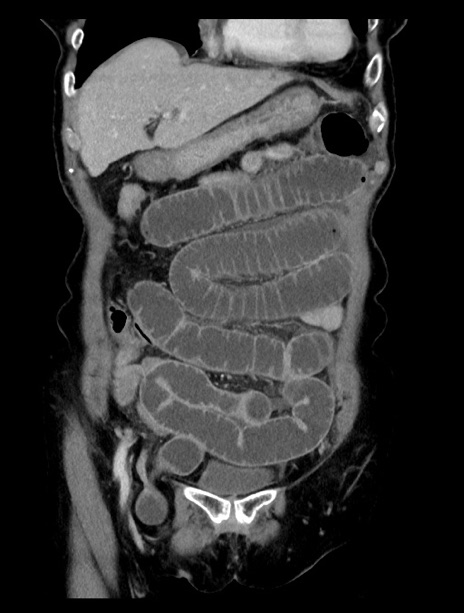

症例23(冠状断像)

【症例】70歳代女性

【主訴】下腹部痛・嘔吐

【現病歴】2日前より腹痛あり。昨日嘔吐あり。症状改善しないため来院。

【既往歴】胃GISTに対して胃部分切除後。

【身体所見】BT 37.1℃、BP 128/77mmHg、腹部:平坦・軟、下腹部に圧痛あり。

【データ】WBC 10200、CRP 0.31